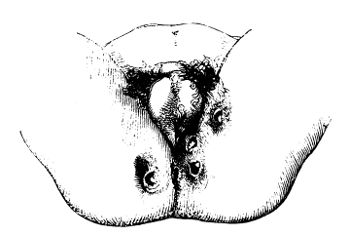

| InjuHemorrhoids or Piles | 445 |

| InjuryDistinct Varieties | 445 |

| InjuInflammation of the Rectum | 447 |

| InjuFistula | 449 |